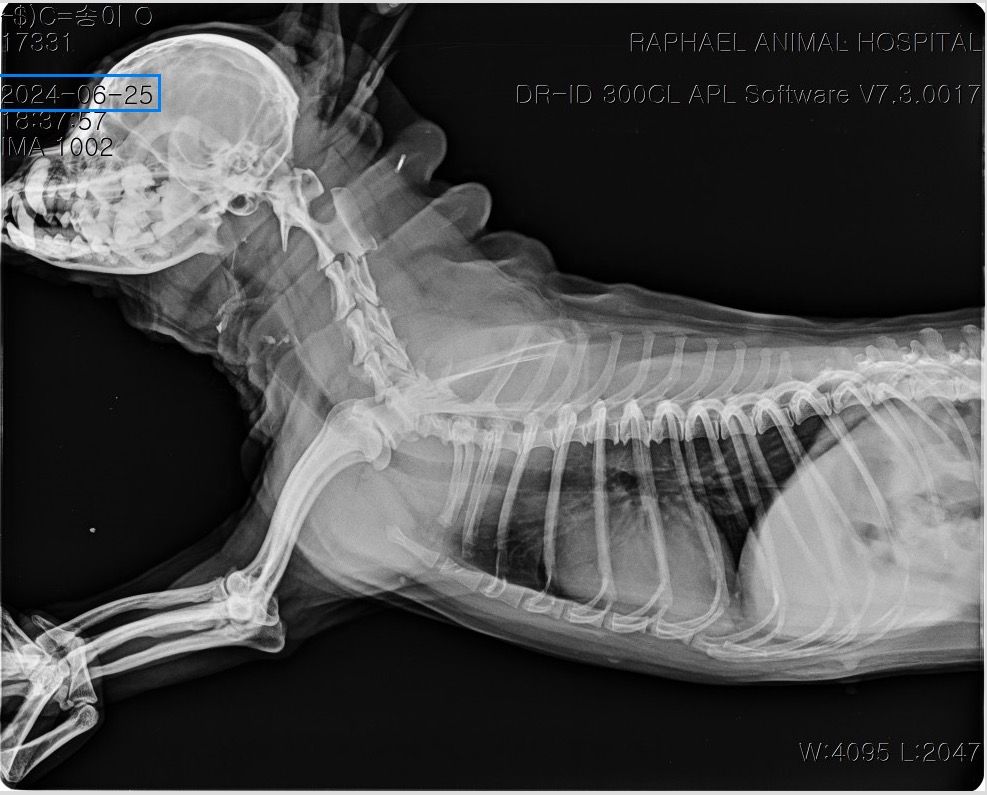

말씀주신 것처럼 보여주신 방사선에서 흉강 내 종양 (폐, 흉강 등)이 의심되는 상황입니다. 다만 방사선 사진만으로는 종양 여부와 정확한 위치, 개수, 성격을 완전히 판단하기 어렵고 CT 촬영을 통해 정확한 판단이 이루어져야 수술 여부 등을 결정할 수 있습니다. 좌측 폐는 앞엽과 뒷엽으로 나눠지긴 하고, 사진 상으로는 좌측 뒷엽 혹은 오른쪽 폐와 왼쪽 폐 사이에 있는 덧엽 부분에도 종괴가 위치하는 것으로 보이지만, 방사선으로는 어느 폐엽에서 발생한 것인지 정확히 구분할 수는 없습니다.

종괴가 단일 병변인지 여러 개인지, 정확히 어느 폐엽에서 시작되었는지, 주변 조직이나 다른 폐엽으로 이어져 있는지,

원발성 종양인지 전이성 병변인지 등을 알려면 CT 촬영이 필요하며 치료 방향도 CT 결과에 따라 달라집니다. 만약 한 두개의 폐엽에 국한된 단일 종괴라면 경우에 따라 해당 폐엽을 제거하는 수술을 고려하는 경우가 있습니다. 하지만 주변 조직으로의 침습, 원격전이 혹은 너무 많은 엽을 포함하고 있어 수술 후 호흡 합병증이 예상되는 경우 수술로 완치 기대는 어렵습니다. 빠른 CT 촬영을 추천드립니다.

사진상으로는 상당히 전형적인 원발성 폐종양의 방사선 양상이지만 말씀 하신 "방사선 엑스레이 촬영 한 것을 통해서서도

폐 종양인지 아닌지, 갯수를 확인가능한지

한 폐엽에만 있는 상황인건지 아니면 윗쪽 중간 폐엽과도 이어져있는지 원발성,악성 등등"에 해당하는 내용은 방사선 사진으로 평가하는게 아닌 흉부 CT검사로 확인해야 하는 사항들입니다. 흉부 방사선 검사는 저렴하지만 정확도와 세밀한 내용 평가에 제한이 있습니다. 우선 주치의와 상의하시고 흉부 CT검사를 촬영 한 후에 침습이나 전이 여부 평가하고 수술 계획 잡으시기 바랍니다. 원발성 폐종양인 경우 악성이더라도 수술로도 완치가 가능한 몇 안되는 질환이니 수술을 빨리 하면 할 수록 좋을 수 있으니 아이에게 주워진 시간을 아끼시기 바랍니다.